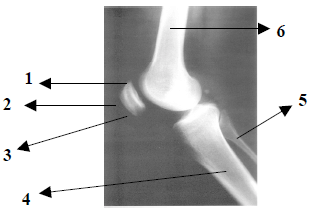

Observe atentamente a imagem radiográfica abaixo e responda:

Pela anatomia radiológica demonstrada na imagem, podemos afirmar que trata-se da incidência